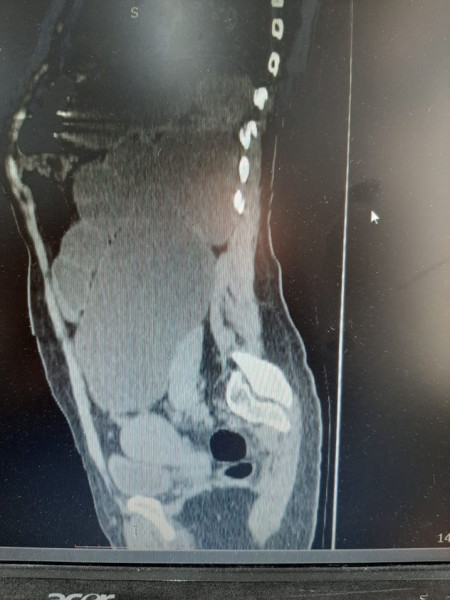

ويتابع قائلا:" وصلت المريضة الى قسم الطوارىء بالمستشفى تشكو من آلام فى الخاصرة اليسرى وتم تحويلها إلى عيادة المسالك البولية فى العيادة الخارجية،وبعد الفحص الإكلينيكيى اولا، لوحظ انتفاخ كبير فى حجم البطن فى الجانب الأيسر ،ومن ثم أجريت لها صورة تليفزيون وصورة مقطعية التى أظهرت وجود أكياس بها صديد وبأحجام كبيرة جدا.التشخيصي(Non functioning Lt kidney).

وأكد أبو معمر أن استمرار وجود هذه الاكياس على الكلية دون استئصالها مع الكلية سيسبب لها تسمم دموي فى الفترة المقبلة،لذلك تم اجراء عملية للمريضة واستئصال كامل الكلية اليسرى بالمنظار الجراحى مع استئصال الأكياس التى كانت ممتلئة بالعديد قدر ب (2) لتر.(Laparoscopic simple nephrectomy).